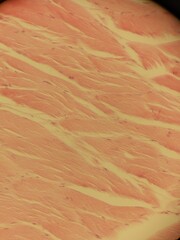

Podobny obraz Orange Gradient Crumpled Paper Texture Background